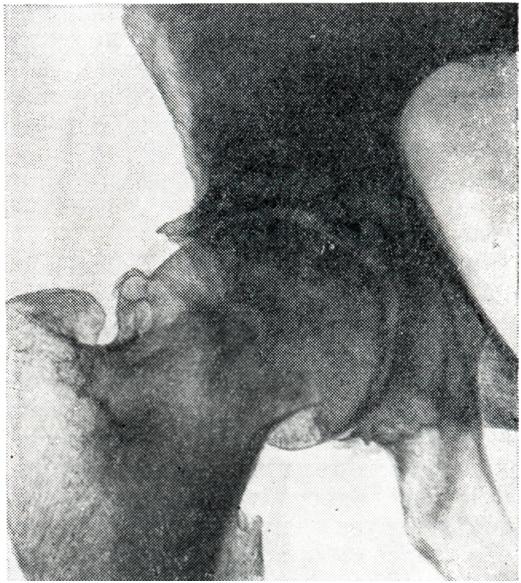

Рис. 13.

Артроз тазобедренного сустава (III стадия). Сужение суставной щели, краевые остеофиты (рентгенограмма).

Вторичные коксартрозы чаще неодинаково поражают оба сустава или бывают односторонними. Первичные же обычно симметричны. В отличие от других локализаций артрозов, при коксартрозах наблюдается четкая корреляция между клиническими симптомами и рентгенологическими изменениями, причем иногда даже клинические симптомы появляются в первую очередь. Боли при ходьбе и хромота вначале появляются только к концу рабочего дня, позднее держатся весь день, а в тяжелых случаях настолько интенсивны, что мешают больному заснуть, иррадиируют в коленный сустав, в седалищную и паховую область. Ограничение подвижности наступает рано. Больной вынужденно держит ногу в положении флексии, аддукции и внешней ротации. Попытка разогнуть, отвести или повернуть бедро кнутри причиняет сильную боль. Для компенсации флексионной контрактуры развивается поясничный лордоз. В результате указанных деформаций нога кажется укороченной. На рентгенограмме (рис. 13) видны все характерные для артроза изменения: сужение суставной щели (по всему суставу или только в верхней его части), подхрящевой склероз (как со стороны головки бедренной кости, так и со стороны вертлужной впадины), краевые остеофиты (также в области обеих суставных поверхностей) и костные кисты (как в эпифизарной части головки бедра, так и в тазовых костях).